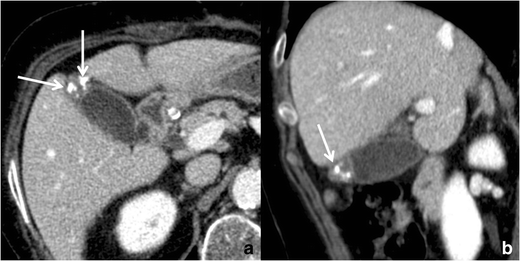

RAS typically appear markedly hyperintense on T2-weighted images (Fig. 10) [29], hypointense on T1-weighted images and show no contrast enhancement. Anyway, progressive bile concentration and calcification development may change the MRI appearance of RAS that may become increasingly hyperintense on T1-weighted images (Fig. 11) and relatively hypointense on T2-weighted ones.

Fig. 10

Gallbladder adenomyomatosis: typical MRI findings. On MRI, GA can be identified as a mural thickening (line) containing small T2-hyperintense spaces representing RAS (arrows). RAS can be better identified on fat-saturated T2-weighted images (b) than on non-fat-saturated ones (a)

Fig. 11

MRI of gallbladder adenomyomatosis: T1-hyperintense Rokitansky–Aschoff sinuses. Rokitansky–Aschoff sinuses (arrow) may appear hyperintense on T1-weighted images if containing concentrated bile or calcifications

The use of fat-saturated T2-weighted sequences increases RAS conspicuity.